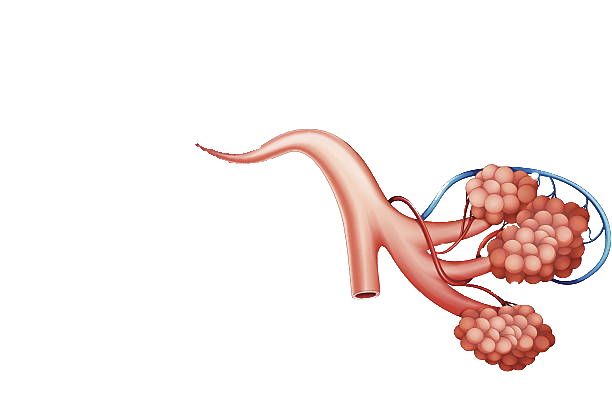

- Sistemi i frymëmarrjes

- Frymëthithja dhe frymënxjerrja

- Frymëmarrja tek qelizat